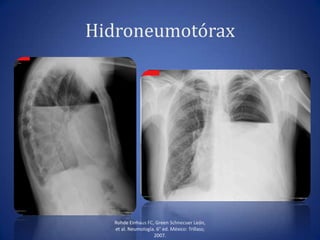

• Cuando además de líquido, existe aire en la cavidad

pleural (fístula broncopleural o introducción accidental

de aire a la cavidad pleural durante una punción).

• Líquido se acumula en las partes declives y el aire en la

parte superior.

Hallazgos radiológicos de

hidroneumotórax

• Opacidad homogénea que

borra senos

costodiafragmáticos,

cardiofrénicos y diafragma.

• Nivel hidroaéreo.

• Desplazamiento de la sombra

mediotorácica hacia el lado

contrario.